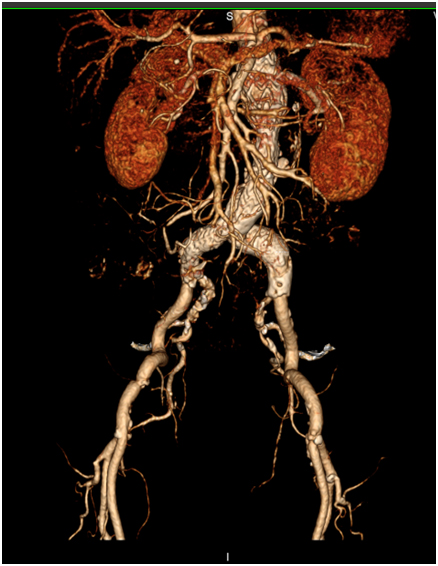

术后造影显示腹主动脉瘤完全隔绝,双侧肾动脉及肠系膜上动脉血流通畅,各脏器未见明显缺血,患者无腹痛,无肾功能损害,肌酐尿素氮未见升高。一星期后复查CTA显示支架位置良好,未见明显内漏,双肾动脉及肠系膜上动脉未见明显狭窄或闭塞。患者顺利康复出院。

术前CTA三维重建结果